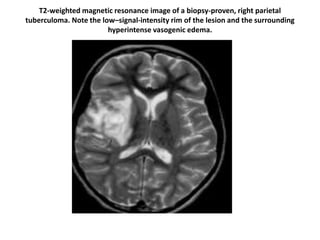

T2-weighted magnetic resonance image of a biopsy-proven, right parietal

tuberculoma. Note the low–signal-intensity rim of the lesion and the surrounding

hyperintense vasogenic edema.

T2-weighted magnetic resonanceimage of a biopsy-proven, right parietal tuberculoma. Note the low–signal-intensity rim of the lesion and the surrounding hyperintense vasogenic edema.